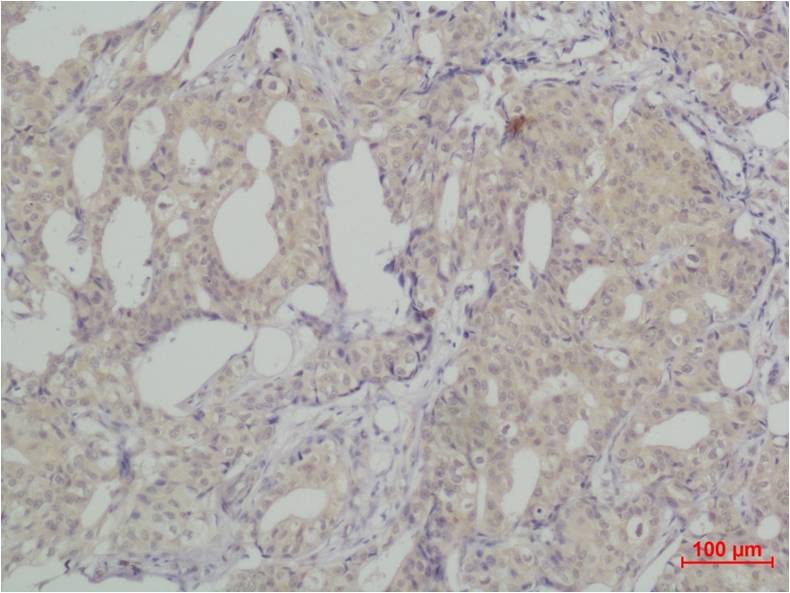

分类: 科研抗体货号: P23177别名: MTB; CAPG2; LUZP5; CAP-G2; hCAP-G2应用: IHC反应种属: Human